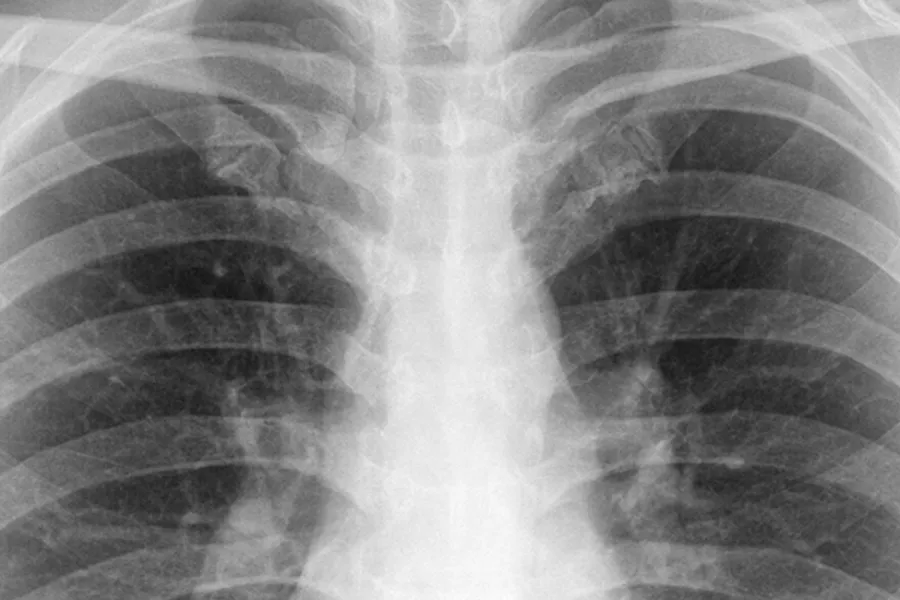

Eit røntgenbilete syner korleis vi ser ut inne i kroppen. Bileta ser heilt annleis ut enn eit vanleg foto, difor er det mest dei som jobbar på sjukehuset som skjønner kva dei ser på bileta. For andre ser bileta grå ut.